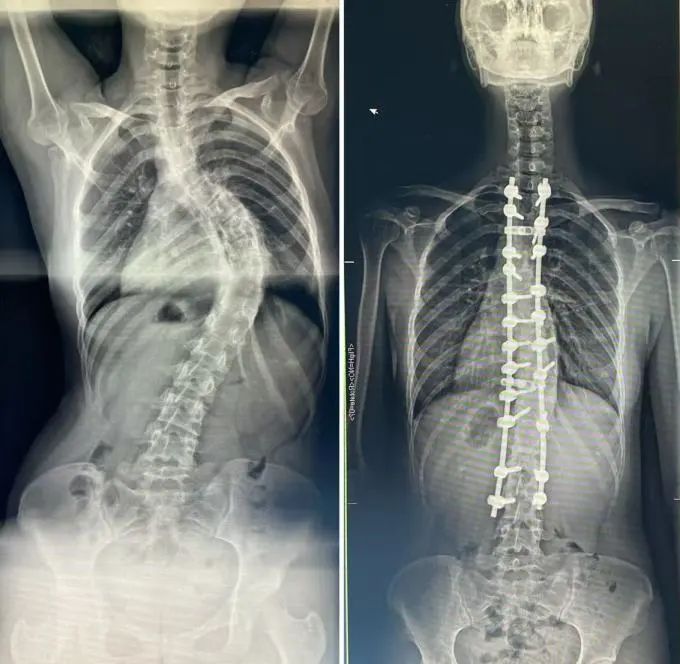

时光回溯至2015年,那时的林玥正被严重的脊柱侧弯所困扰,弯曲程度已达80°,这不仅严重影响了她的日常生活,更让她的心灵蒙上一层阴影。

命运的转折点在2015年来临。在福州大学附属省立医院(福建省立医院),林玥接受了由我院徐杰教授主刀的脊柱侧弯矫正手术。这次手术不仅重塑了她的脊梁,更改变了她的人生轨迹。

△手术前(左)和手术后(右)